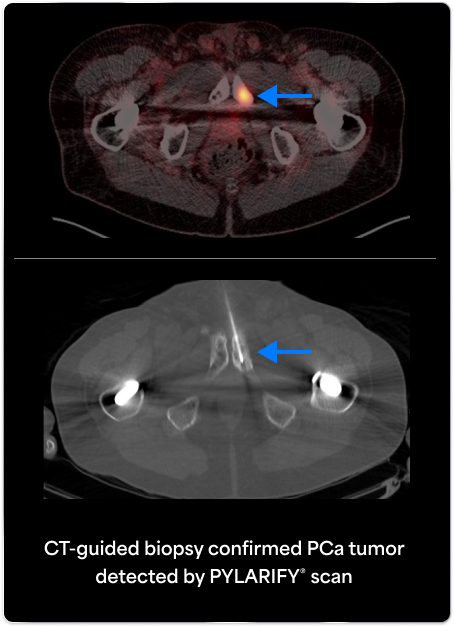

PYLARIFY prompted treatment change from prostatectomy to systemic therapy, thereby avoiding undertreatment